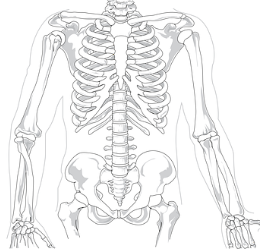

우선 고관절이라는 곳이 어디인지 정확하게 알아보자면 골반과 허벅다리의 만나는 지점을 고관절이라 하는데 이 두 곳을 이어주는 역할을 합니다. 종종 고관절을 골반과 비슷한 곳으로 알고 계시는 분이 계신데 이는 엄연하게 다른 부분입니다.